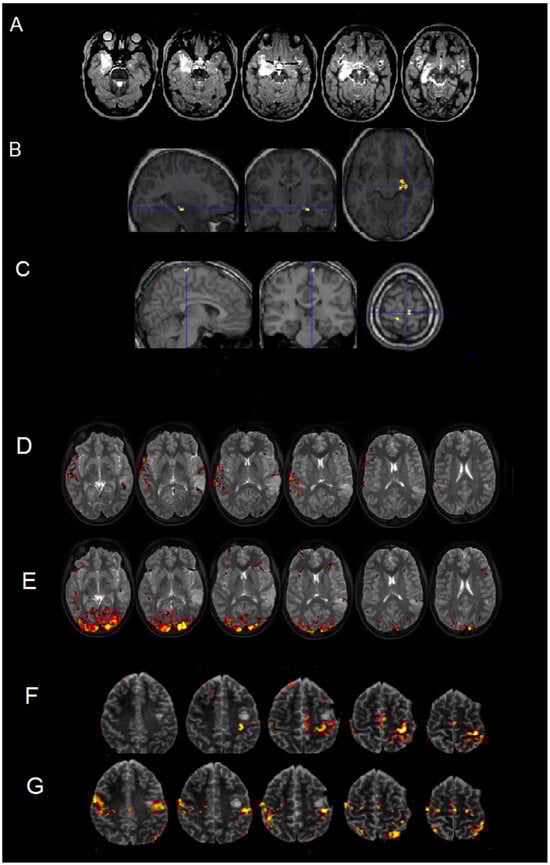

What Can Neurosurgical Pediatric Populations Do in Functional Magnetic Resonance Imaging? Brain Activity Mapping Before Intervention Tasks, a Retrospective Study

by Ilaria Guarracino, Marta Maieron, Serena D’Agostini, Miran Skrap, Paola Cogo, Tamara Ius and Barbara Tomasino

Background/Objectives: Performing presurgical functional magnetic resonance imaging (fMRI) mapping in young patients is considered a challenge for clinicians, as fMRI maps are the sole source of information about the functional organization of cognitive functions/areas, especially when an awake craniotomy is not possible, [...] Read more.

Background/Objectives: Performing presurgical functional magnetic resonance imaging (fMRI) mapping in young patients is considered a challenge for clinicians, as fMRI maps are the sole source of information about the functional organization of cognitive functions/areas, especially when an awake craniotomy is not possible, as is often the case for pediatric populations. The literature on the fMRI tasks used in pediatric populations with brain injuries shows a certain heterogeneity in the approaches (task-based or resting states) and tasks, with a preference for motor/language mapping: tasks assessing extra-language functions are lacking. Methods: We have designed fMRI tasks focused on language and extra-language functions, which can be easily be applied when clinicians need to perform presurgical mapping. We present a retrospective case series of 17 patients. Results: Seventeen young patients (13.4 ± 2.8 years; range 7–16) were included in the study, for whom fMRI was performed. All underwent successful fMRI mapping by completing fMRI tasks selected based on their lesion site. The number of tasks performed by each patient significantly correlated with their age (r(17) = 0.561, p = 0.019). The patients tolerated the assessment and had good motion control: their movement parameters were minimal (range of rotation of −0.015–0.01 degrees; range of translation of −0.8–0.2 mm). The most administered fMRI tasks were tongue motor localizer (60%) and object naming (70%), with some patients performing extra-language function mapping involving visuo-spatial processing, selective attention, memory, and inhibition. Conclusions: This is an exploratory study given the sample size. fMRI measurements were considered feasible, as patients were able to complete the tasks under clinically realistic conditions. We discuss the clinical implication/usefulness of administering tasks for a personalized functional assessment of the young patient before surgery. Full article

Figure 1